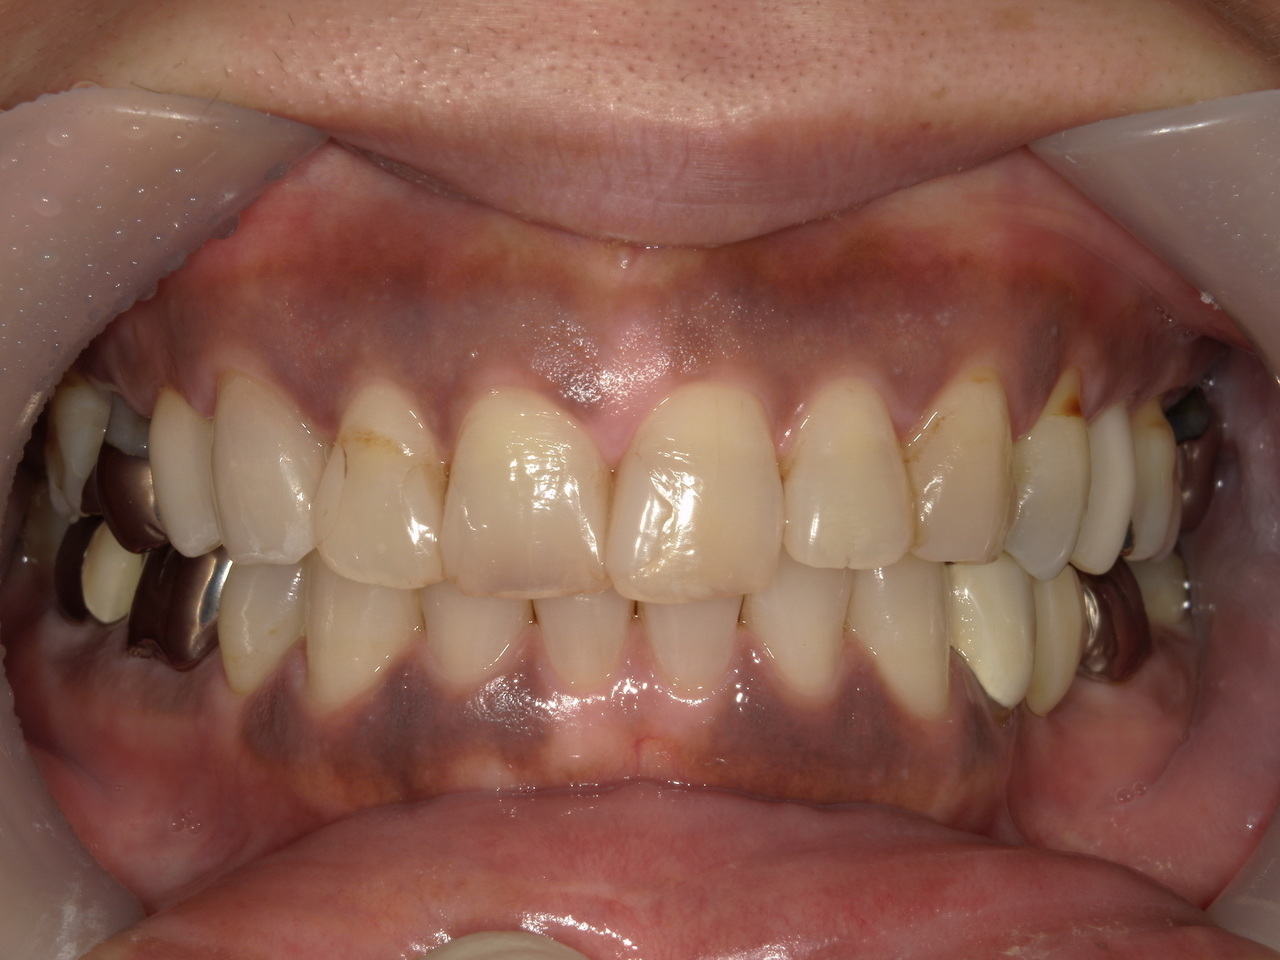

歯肉に喫煙によるメラニン沈着が

認められます。